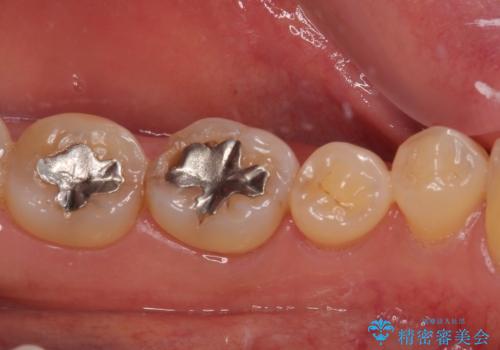

ゴールドインレーは銀歯のインレーやセラミックインレーと比べ、「技工操作の精度が高く、適合が著しく良い」というメリットがあります。特に「適合の良さ」は再治療のリスクを防ぐ上でとても重要な要素となります。

咬み心地はとても良好で、全く違和感がなく、患者様には大変満足していただきました。